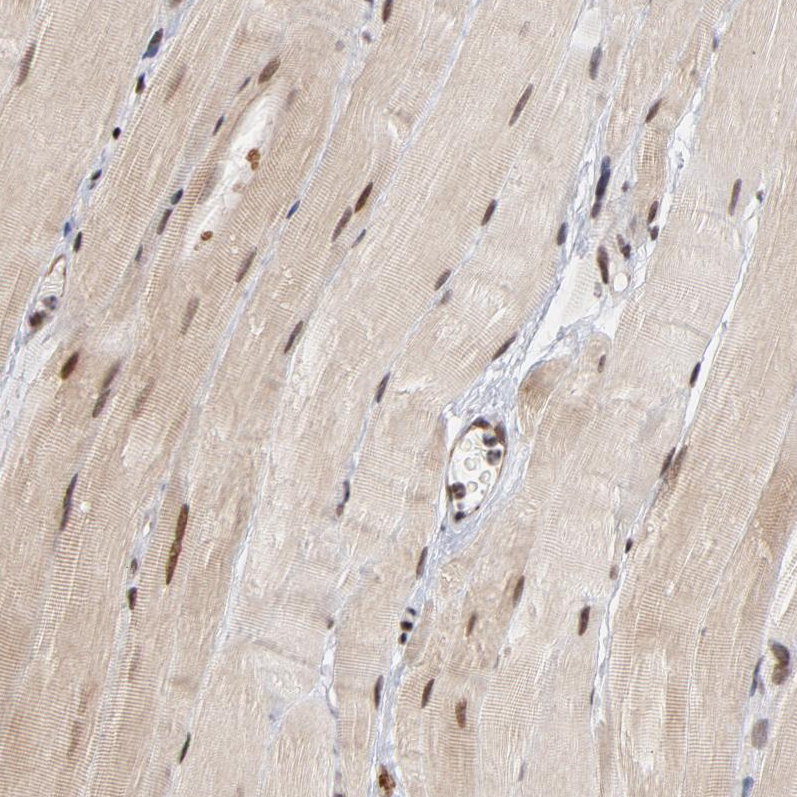

Immunohistochemical staining of human colon shows strong nuclear and moderate cytoplasmic positivity in glandular cells.